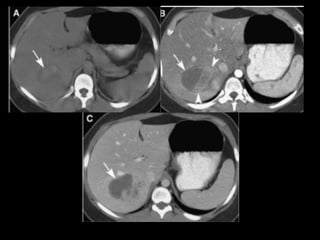

• LA TOMOGRAFIA TIENE EL MAYOR EFECTO.

• VALORACIÒN INICIAL.

• VER LOCALZACIÒN Y EXTENSIÒN

TRAUMATISMOS

• LAS LESIONES TRAUMATICAS PUEDEN SER :

– CONTUSIONES

– DESGARROS

– HEMATOMAS

– ROTURAS

– LACERACIONES

• EN TC :

CONTUSION SIN ROTURA SE MANIFIESTA COMO

IMAGEN HIPODENSA EN CONTRASTADA ESTO

PUEDE SER POR EDEMAS Y HEMORRAGIAS

MICROSCÒPICAS

DESGARRO HEPATICO

TRAUMATISMO: INJURIA HEPATICA